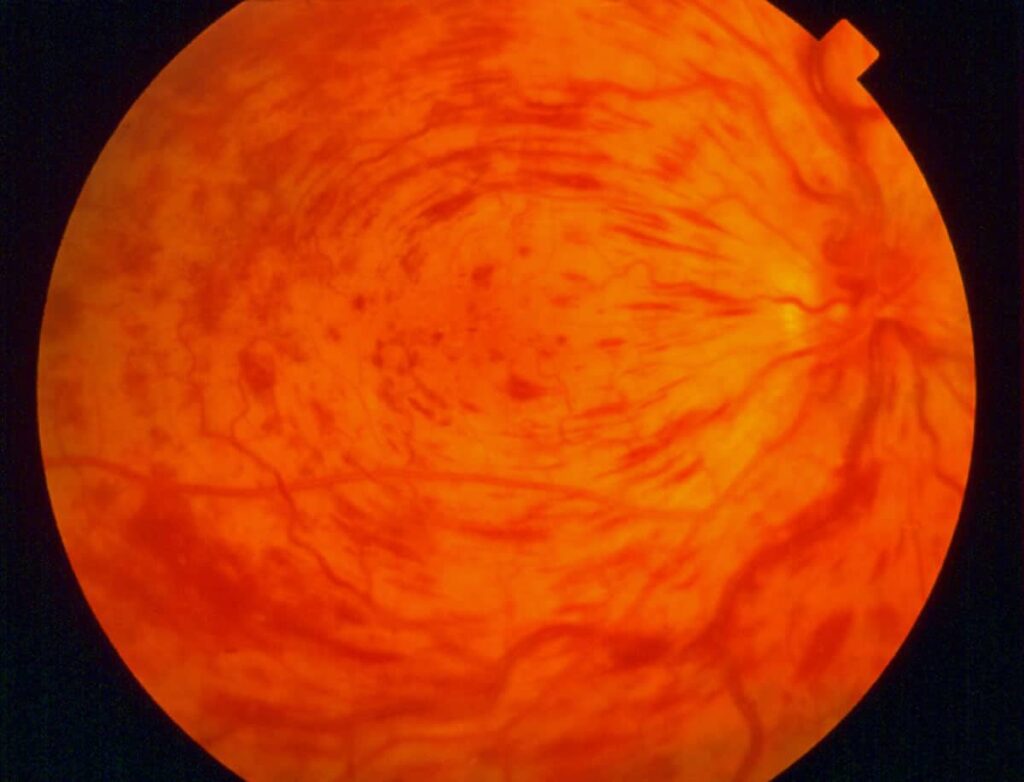

Retinal vein occlusion, or RVO, is what happens when a vein in your retina is blocked. This blockage occurs in a small blood vessel that is designed to carry blood away from your retina. When this blood is not carried away, patients can experience issues with their eyes, including blurry vision, swelling, or bleeding. If left untreated, retinal vein occlusion can lead to vision loss.

- Central retinal vein occlusion (CRVO): This type of RVO blocks the main retinal vein.

- Branch retinal vein occlusion (BRVO): As the most common form of RVO, this type of RVO will block smaller branch veins.